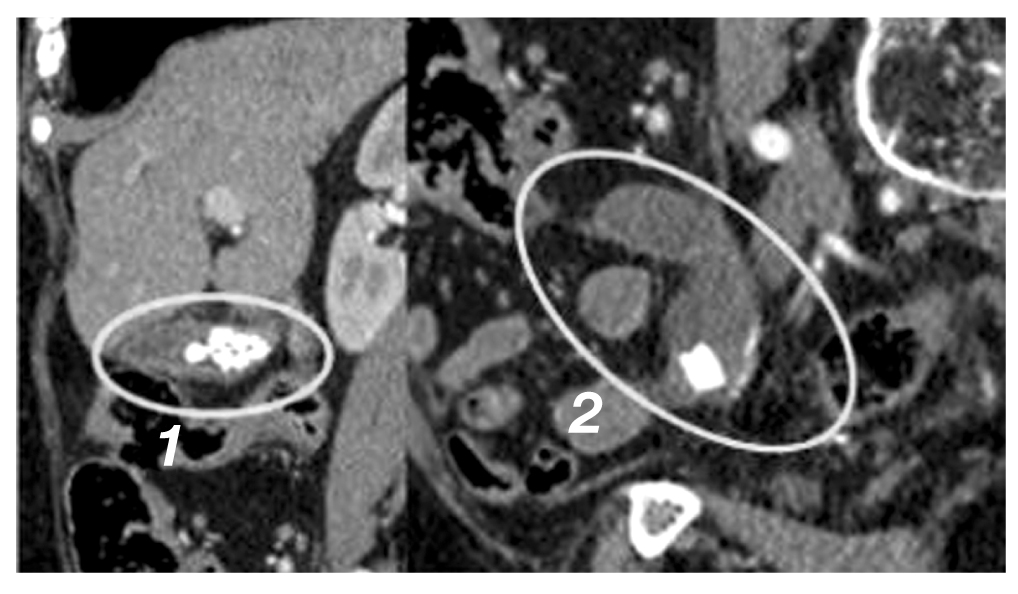

Из анамнеза известно, что в июле 2020 года при диспансерном наблюдении по данным ультразвукового исследования органов брюшной полости у пациентки выявлены кистозное образование малого таза и калькулёзный холецистит. При компьютерной томографии органов брюшной полости с внутривенным контрастированием обнаружены кистозная опухоль червеобразного отростка размером 70×50 мм с наличием кальцинатов в стенке и калькулёзный холецистит (рис. 1). При динамическом наблюдении через 3 года отмечена отрицательная динамика в виде клинической симптоматики и увеличения в размерах кистозной опухоли. Магнитно-резонансная томография органов брюшной полости (апрель 2023 года) показала кистозную опухоль червеобразного отростка размером 106×70 мм с наличием кальцинатов и калькулёзный холецистит (рис. 2).

Рис. 2. Магнитно-резонансная томография органов брюшной полости в динамике через 3 года: кистозная опухоль аппендикса диаметром около 10 см.

Fig. 2. Magnetic resonance imaging of the abdominal organs in the dynamics after 3 years: A cystic tumor of the appendix with a diameter of about 10 cm.